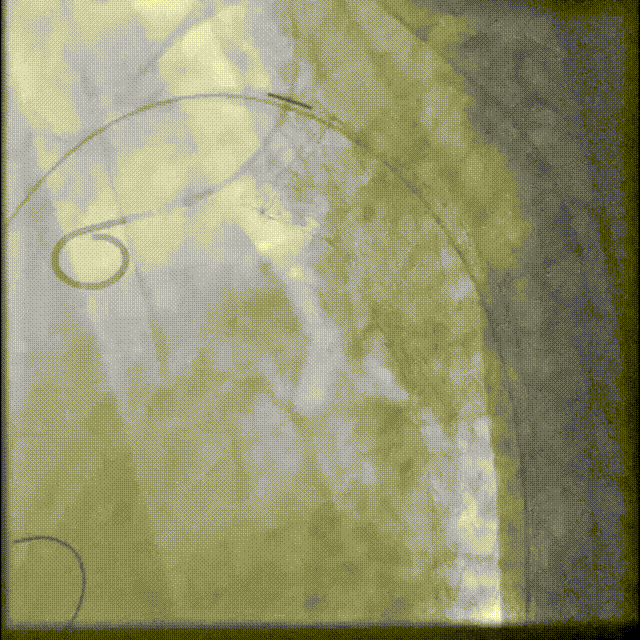

5.第二次拉线释放后支架从远端至近端打开至全直径,支架位置精准形态良好,微调角度控制旋钮,使支架小弯侧贴壁更佳。完成后续释放操作后进行主动脉弓部造影。

gore医疗怎么样「胸有乾坤」可调可控 分毫必争—GORE®TAG® 可主动调控胸主动脉覆膜支架治疗B型主动脉夹层伴升主动脉瘤病例报道_https://www.jmylbn.com_新闻资讯_第11张

全直径释放

gore医疗怎么样「胸有乾坤」可调可控 分毫必争—GORE®TAG® 可主动调控胸主动脉覆膜支架治疗B型主动脉夹层伴升主动脉瘤病例报道_https://www.jmylbn.com_新闻资讯_第12张

主动调控支架小弯侧贴壁

gore医疗怎么样「胸有乾坤」可调可控 分毫必争—GORE®TAG® 可主动调控胸主动脉覆膜支架治疗B型主动脉夹层伴升主动脉瘤病例报道_https://www.jmylbn.com_新闻资讯_第13张

释放后造影

6.假腔未见显影,弓上分支通畅,导管移至降主段造影,内脏分支第一时间显影,结束手术,患者移至ICU继续观察。患者后续转至心外科进行Bentall手术,该部分不再详述。